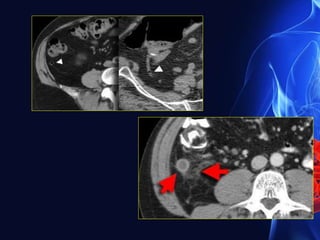

CT findings in acute appendicitis

90% diagnostic accuracy to detect acute appendicitis

• An appendix measuring greater than 6 mm in diameter

• Failure of the appendix to fill with oral contrast or air up to

its tip

• An appendicolith

• Enhancement of its wall with intravenous contrast

• Surrounding inflammatory changes include increased fat

attenuation, fluid, inflammatory phlegmon, caecal

thickening, abscess, extraluminal gas and

lymphadenopathy

Acute appendicitis. CT

showing an appendix which

contains a dense

Appendicolith

Appendix inflammatory mass. CT

shows soft- tissue density in the

right iliac fossa containing an

Appendicolith..